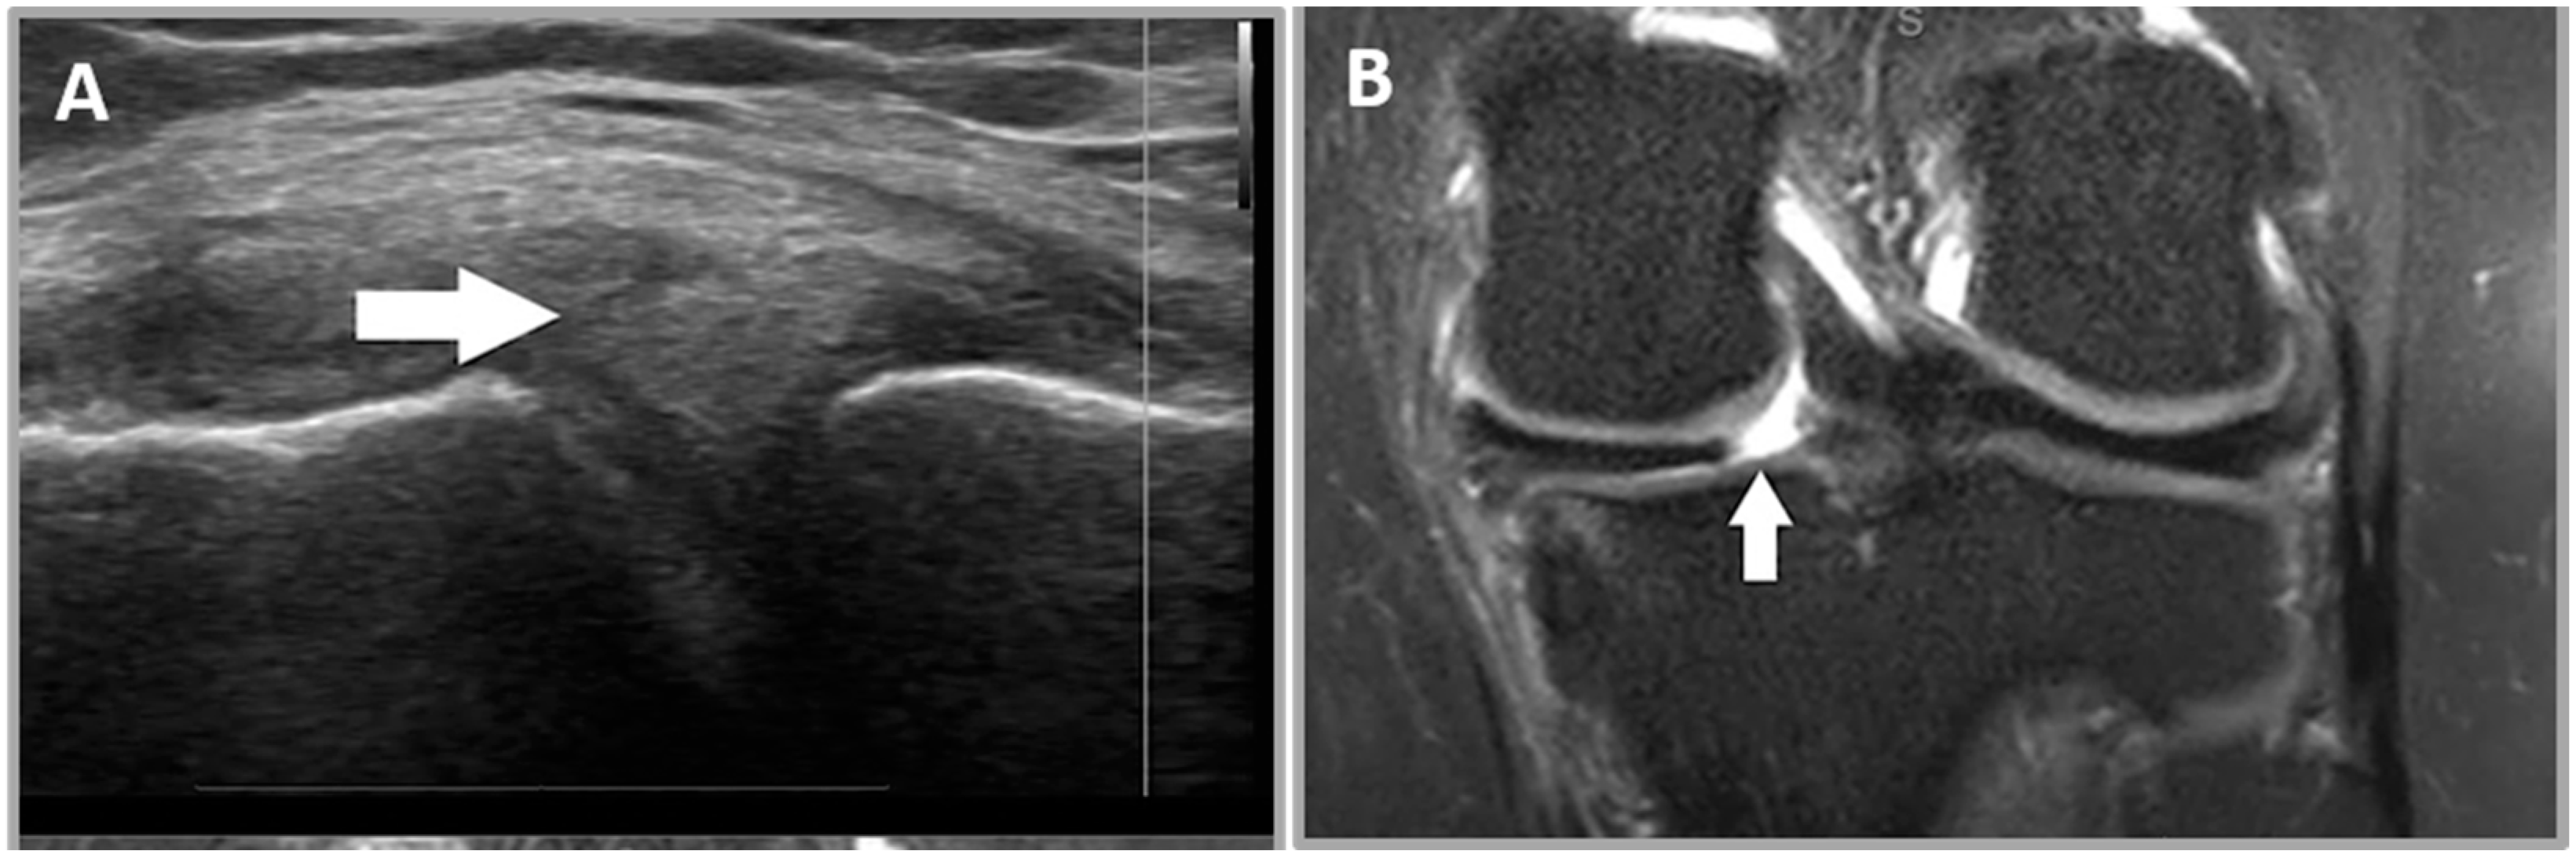

2.5.1. Criterion 1—Meniscal Cleft

2.5.2. Criterion 2—Parameniscal Cyst